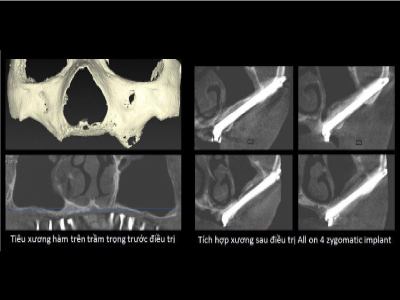

Cấy ghép Implant xương gò má cải tiến cho người tiêu xương trầm trọng (2014). Công trình đã được báo cáo tại hội nghị quốc tế về Phẫu thuật Miệng và Hàm Mặt (ICOMS) tại Úc 2015, Hồng Kông 2017 và công bố tóm tắt trên tạp chí International Journal of Oral and Maxillofacial Surgery, 2015 là tạp chí thuộc Hiệp hội quốc tế về Phẫu thuật Miệng và Hàm Mặt (IAOMS)

Cấy ghép Implant xương gò má cho bệnh nhân bị tiêu xương hàm trên trầm trọng

Bệnh nhân L.N.L có xương hàm trên bị tiêu trầm trọng cả theo chiều dọc và chiều ngang, chỉ còn một vài milimet, vùng răng sau xương hàm xuống thấp. Ts.Bs Võ Văn Nhân đã thực hiện kỹ thuật cấy Implant xương gò má. Đây là phương pháp rất khó vì Implant có lộ trình dài, nằm gần các cấu trúc giải phẫu quan trọng như màng xoang hàm, thần kinh dưới ổ mắt, sàn ổ mắt,…